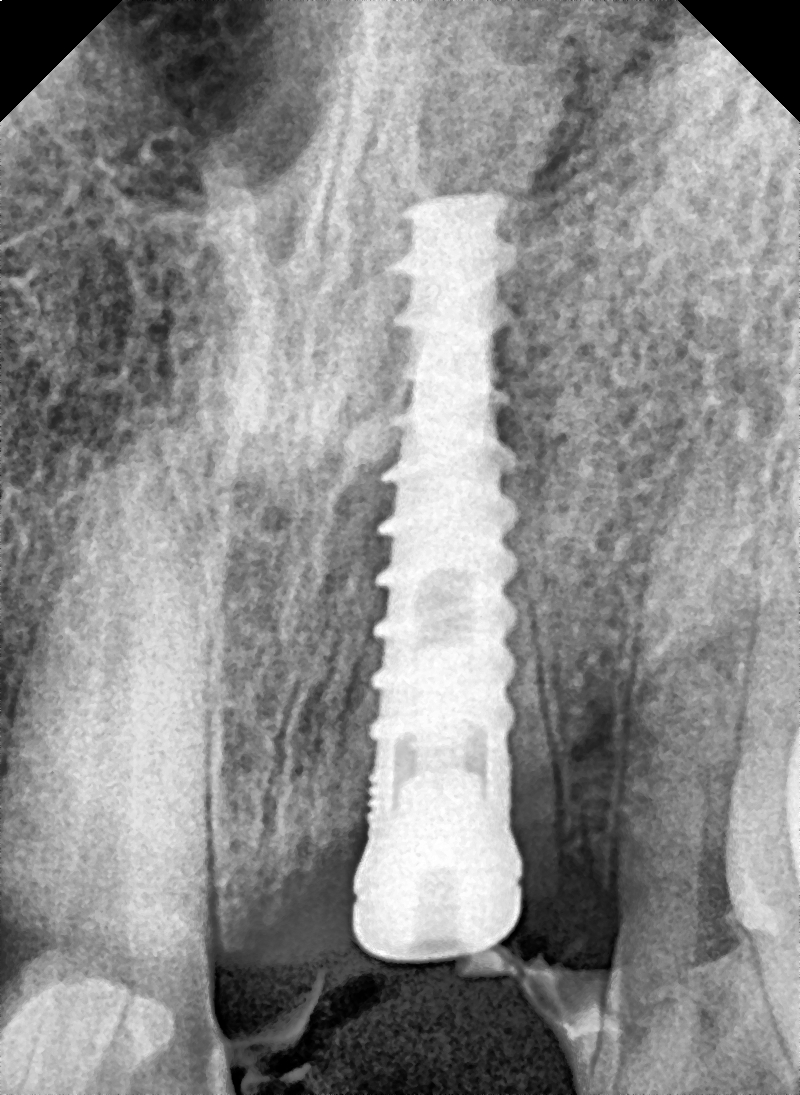

Images Of Dental Treatment Servcies Done At Our Hospital